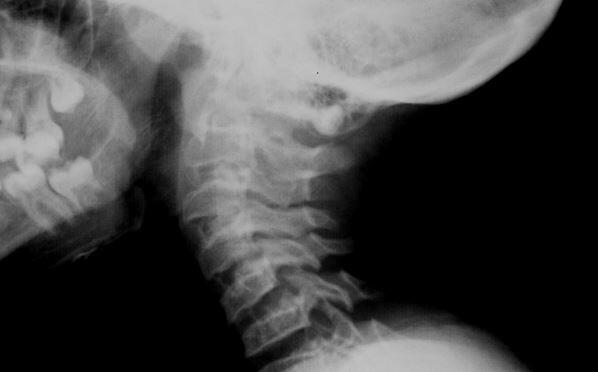

Servikal Lordoz Düzleşmesine Genel Bakış Boynumuz, anatomik olarak başın agırlığını taşıyan, başı gövdeye bağlayan ve başın duyusal işlevini yerine getirmek amacıyla gereken hareket açıklığına olanak ...